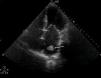

Após reperfusão, a doente mantinha sinais de hipoperfusão restritos aos membros inferiores. Este achado, aliado ao difícil acesso femoral, motivou a realização de aortografia, que evidenciou oclusão trombótica da aorta abdominal infrarrenal com extensão às ilíacas (Figura 3). No ecocardiograma visualizava‐se uma massa na aurícula esquerda, compatível com trombo (Figura 4). Foi efetuada tromboembolectomia do eixo ilíaco esquerdo e pontagem femoro‐femoral; contudo, a doente evoluiu com quadro de disfunção multiorgânica com desfecho fatal.